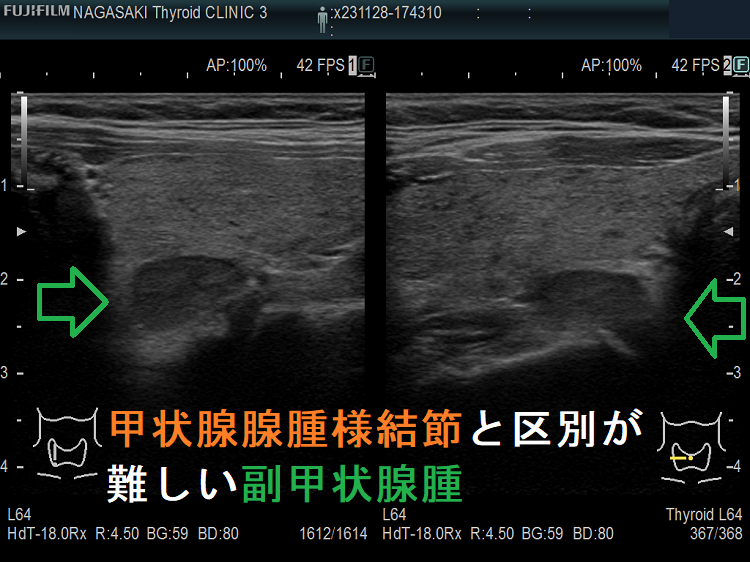

甲状腺内副甲状腺腫は、超音波(エコー)検査で甲状腺腫瘍と形態的に鑑別できない場合があります(実際は下の写真のように診断できていますが・・)。特徴的な超音波(エコー)所見は、腹側の高エコーで感度86%、特異度100%です[Surgery. 2012 Dec;152(6):1193-200.]。さらに、99m-Tc MIBIシンチグラフィーで取り込み(集積)があれば甲状腺内副甲状腺腫と診断できます。

腺腫様甲状腺腫に合併する甲状腺内副甲状腺腫

腺腫様甲状腺腫に合併する甲状腺内副甲状腺腫は、腺腫様結節と鑑別が難しいだけでなく、多腺性(5-6腺)のケースがあります。

副甲状腺腺腫と同じような位置(写真では左甲状腺の背側)にあり、甲状腺の中なのか外なのかはっきりしません。副甲状腺腺腫のように見えるも、実は甲状腺の中にある甲状腺腺腫様結節。その他、排液後の甲状腺腺腫様結節も副甲状腺腺腫と同じように見える場合もあります。